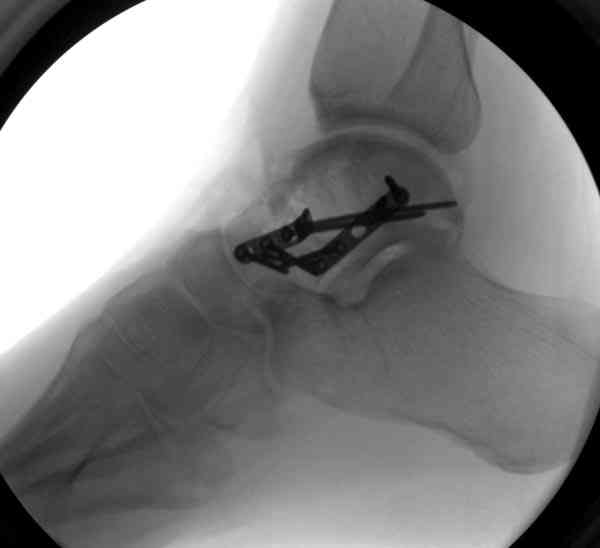

Случай с множественным оскольчатым переломом тарана оперированный из двойного доступа.

Через 14 мес.: